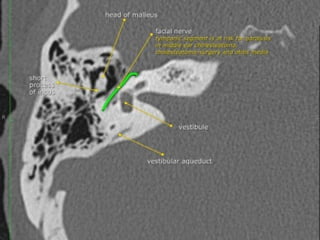

 Intratemporal facial nerv;

CN7 segments: lAC, labyrinthine, tympanic, mastoid segments

Geniculate ganglion = anterior genu

Posterior genu: Tympanic segment bends inferiorly to become mastoid

segment

Facial nerve

 The facial nerve is one of the key cranial nerves with a complex and broad range of

functions.

 Although at first glance it is the motor nerve of facial expression which begins as a trunk

and emerges from the parotid gland as five branches it has taste and parasympathetic

fibres that relay in a complex manner.

 The facial nerve is the only cranial nerve that may show normal post-contrast

enhancement, although this applies only to the labyrinthine segment up to

the stylomastoid foramen. Enhancement of the other segments of the facial nerve and

other cranial nerves is considered pathologic.

Segments

 intracranial (cisternal) segment - zero branches

 meatal (canalicular) segment (internal auditory canal): 8 mm long, zero branches

 labyrinthine segment (IAC to geniculate ganglion): 3-4 mm long, 3 branches

(from geniculate ganglion)

 tympanic segment (from geniculate ganglion to pyramidal eminence): 8-11 mm

long, zero branches

 mastoid segment (from pyramidal eminence to stylomastoid foramen): 8-14 mm long, 3

branches

 extratemporal segment (from stylomastoid foramen to division into major branches): 15-

20 mm, 9 branches